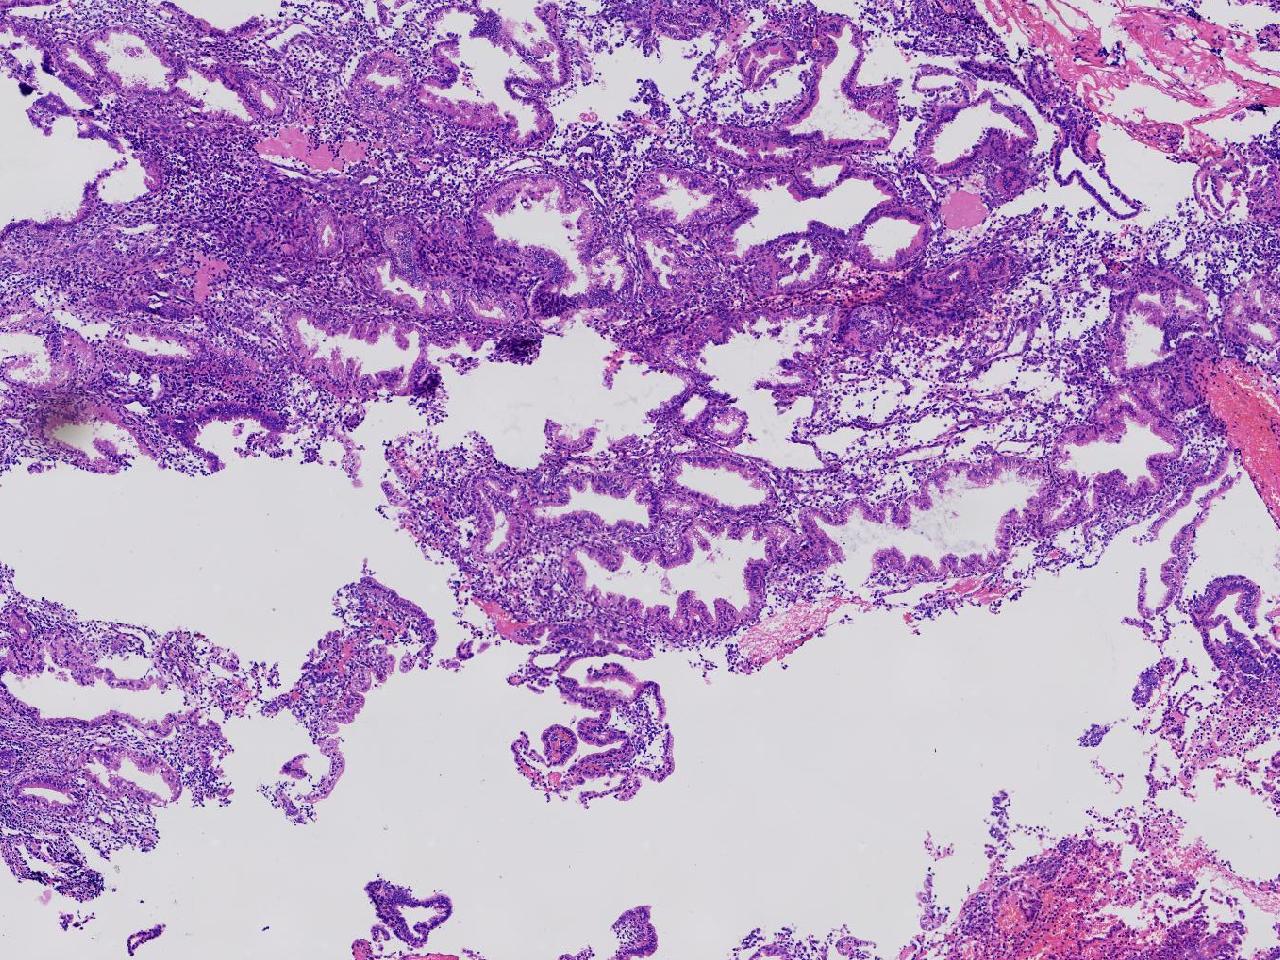

性别

女

年龄

45岁

临床诊断

阴道不规则出血20余天,

一般病史

彩超示:宫腔内见约41X11毫米的不均质回声区。宫腔镜示:宫腔形态正常,内膜粉红,不规则增厚。

标本名称

子宫内膜

大体所见

灰粉色不整形软组织多块,1.5X1X0.6厘米。

分泌反应子宫内膜,伴有出血。

晚泌期及月经早期改变,局部呈啫酸性乳头状化生改变。